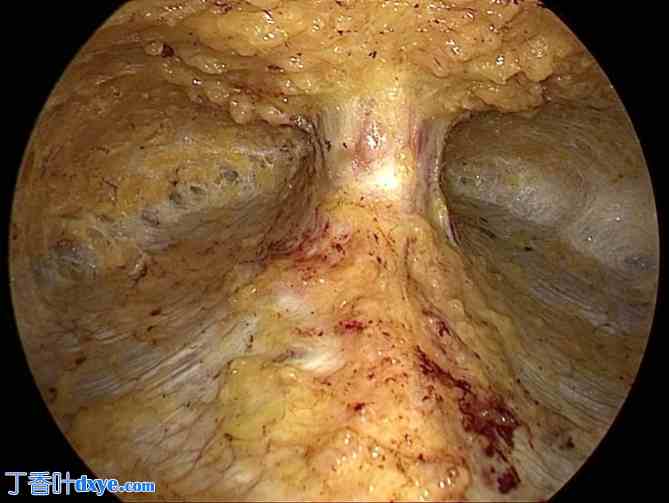

图 3。

3.jpg

解剖的疝囊,看起来像一个花瓶。